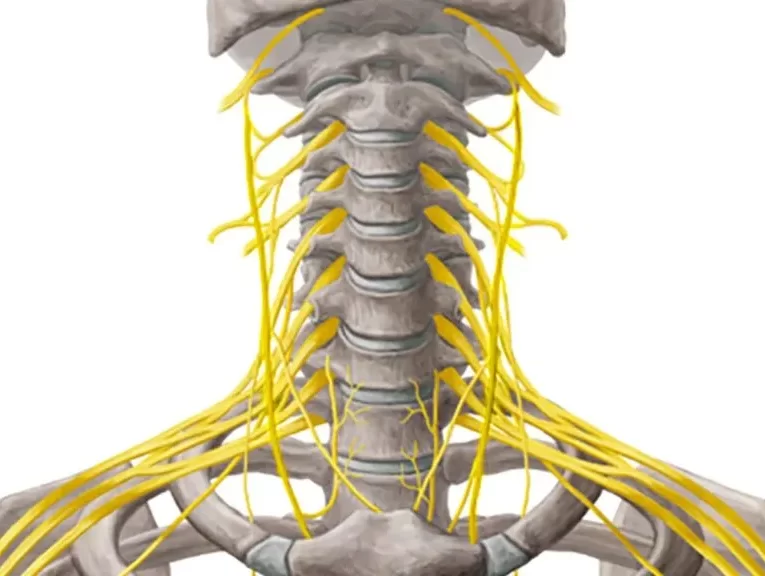

دیسک بین مهرهای ساختاری ژلاتینی است که مانند ضربهگیر عمل کرده و فشار را بین مهرهها توزیع میکند. این ساختار کمک میکند تا مهرهها به نرمی و بدون اصطکاک زیاد بر روی یکدیگر حرکت کنند. در واقع، دیسک نوعی مفصل با ساختاری ویژه است که به حفظ انعطافپذیری و پایداری ستون فقرات کمک میکند.

یکی از مشکلات شایع مرتبط با دیسک، بیرونزدگی دیسک گردن است. این وضعیت میتواند بر اثر فشارهای طولانیمدت یا ناگهانی به گردن، یا به دلیل فرسایش و سائیدگی مفاصل ناشی از افزایش سن رخ دهد. معمولاً پس از سن ۳۵ سالگی، مایع ژلاتینی موجود در دیسکها بهتدریج کاهش مییابد و خشک میشود. این کاهش آب، انعطافپذیری دیسک را کم میکند و موجب سختتر شدن حرکت مهرههای گردن میشود.

هنگامی که دیسک از محل طبیعی خود خارج شود و به ریشههای عصبی یا نخاع فشار وارد کند، این وضعیت به عنوان بیرونزدگی یا فتق دیسک گردن شناخته میشود.

باید بدانید که ستون فقرات که نخاع از داخل آن عبور میکند، شامل تعداد زیادی عصب حسی است که وظیفه کنترل حرکت دست ها و قسمتهای مختلف بدن را بر عهده دارند.

همچنین در قسمت گردنیِ نخاع الیاف عصبی وجود دارند که به سمت پایین امتداد یافته و مسئول ایجاد حس و کنترل ادرار و مدفوع در قسمت پایینتنه هستند.

به همین دلیل دیسک گردن که درست در مجاورت نخاع و عصبهای اصلی بدن است، موضوع بسیار مهمی است که در صورت بروز علائم حتما باید پیگیری و توسط پزشک متخصص بررسی شود.